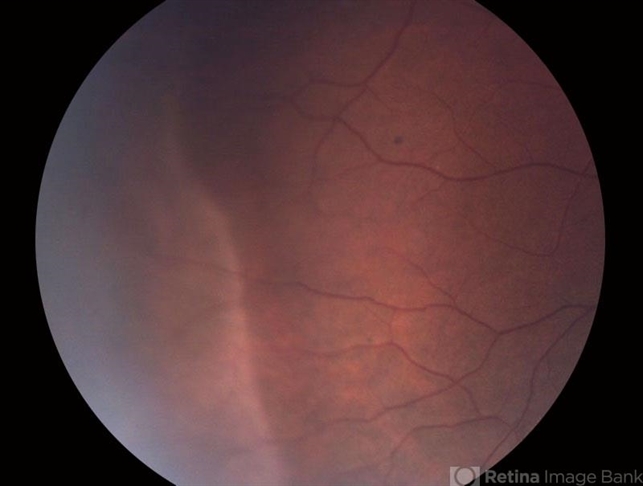

By Gerardo Garcia-Aguirre, MD

Asociacion para Evitar la Ceguera en Mexico - Uploaded on Aug 23, 2012.

- Noemí Hernández, Asociación para Evitar la Ceguera en México

Zeiss FF4 - Description

- Photograph of the temporal peripheral retina showing an area of pale retina (white without pressure).